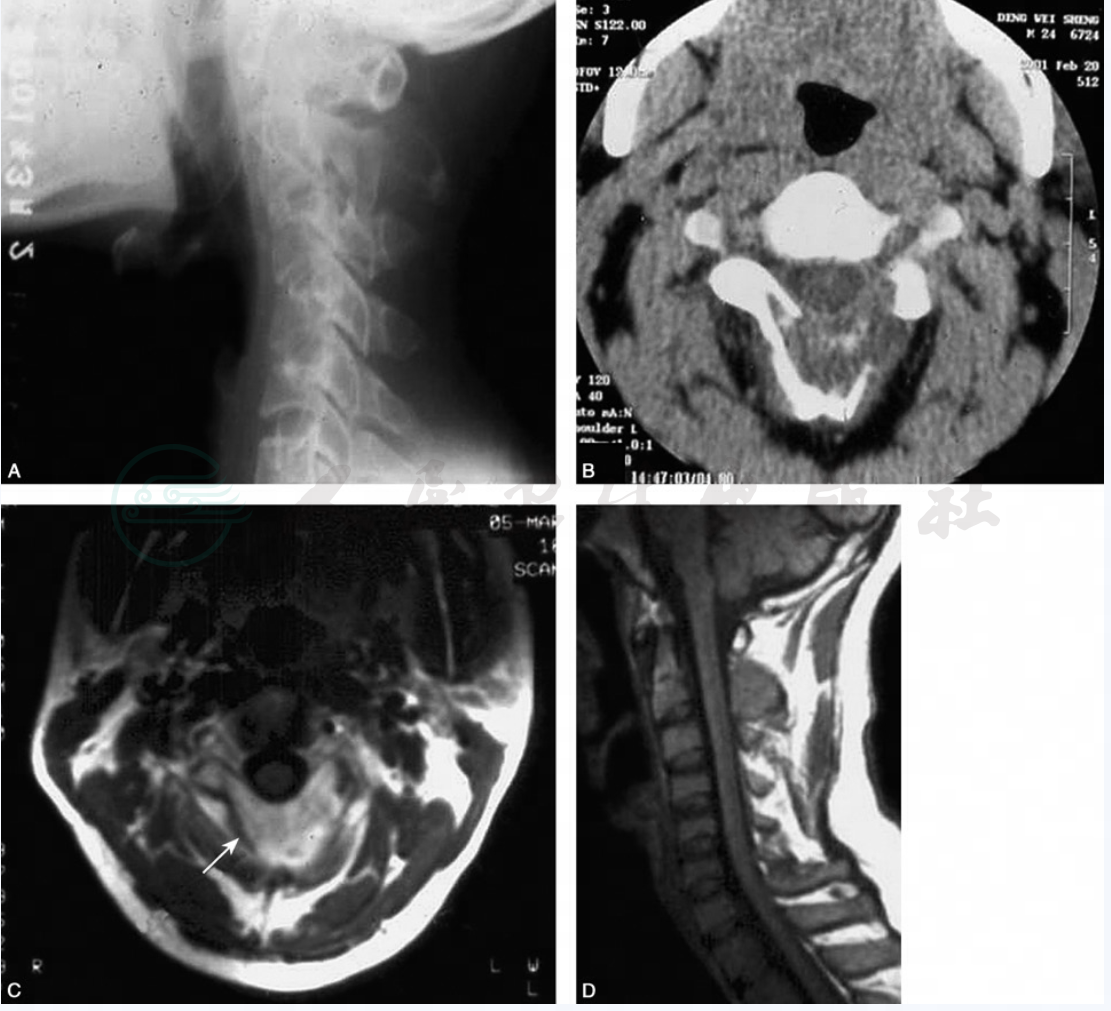

图1枢椎棘突成骨细胞瘤

A. 颈椎侧位X线片示枢椎棘突呈膨胀性骨质破坏; B. 横断面CT示枢椎棘突骨皮质中断,呈膨胀性骨质破坏,内可见斑片状钙化; C~D. 横断面及矢状面MRI示枢椎膨胀性骨质破坏